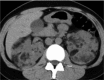

Angiomyolipomas (AMLs) are the most common benign renal tumours. Most of these neoplasms are found incidentally on imaging. However, symptomatic presentation does exist. Renal AMLs are typically composed of smooth muscle, blood vessels, and adipose tissue. Because of the abundant fat tissue, they give a characteristic appearance on imaging and are therefore easily diagnosed. However, sometimes they contain too little fat to be detected. This increases the difficulty in differentiating them from renal cell carcinoma (RCC). Management of AML is based on clinical presentation and should be individualized for every patient. Treatment modalities range from active surveillance to more invasive approaches.